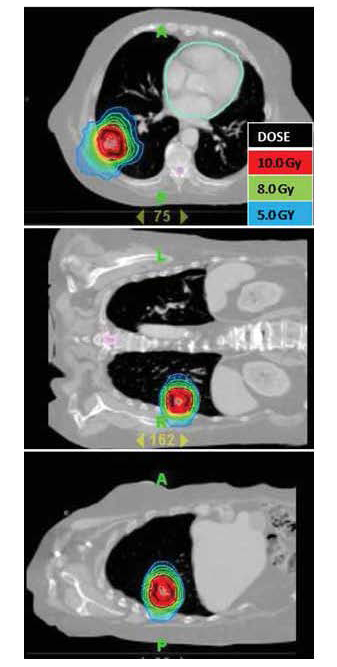

An example of radiosurgery for a Stage I non-small cell lung cancer is seen in figure 6. At this writing (July, 2009) only short-term follow-up is available. The patient tolerated treatment well, suffered no acute toxicities from treatment, and is doing well thus far. It can take from 1 - 6 months to demonstrate a complete radiographic response.

| Figure 6: Medically inoperable patient with Stage I non-small cell lung cancer. The lesion is seen in three views. The patient received SBRT to a total dose of 10.0 Gy times 5 fractions. |